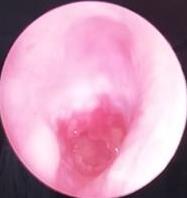

• 耳内镜下软骨-软骨膜复合体用于慢性化脓性中耳炎合并耳真菌病鼓室成形术的疗效分析

2026, 32(1):55-61. DOI: 10.12235/E20240777

摘要 (44) HTML (13) PDF 2.20 M (55) 评论 (0) 收藏

摘要:目的 探讨慢性化脓性中耳炎合并耳真菌病患者行耳内镜下软骨-软骨膜复合体鼓室成形术的临床疗效。方法 选取2021年1月-2023年12月该院收治的,于耳内镜下采用耳屏软骨-软骨膜复合体行鼓室成形术的慢性化脓性中耳炎患者68例,根据是否合并过耳真菌病,将患者分为真菌组和对照组,各34例。真菌组术前合并耳真菌病,均行抗真菌治疗后好转,其中18例合并湿耳;对照组未曾合并过耳真菌病,术前均为干耳。所有患者均接受了耳内镜下鼓室成形术,采用软骨-软骨膜复合体修复穿孔。术后随访至少3个月。于术前和术后3个月,检查纯音听力。观察两组患者鼓膜修补成功率、听力改善情况和干耳时间。结果 真菌组和对照组的鼓膜修补成功率分别为88.24%(30/34)和91.18%(31/34),差异无统计学意义(P > 0.05);两组患者术后3个月气骨导间距明显小于术前,差异有统计学意义(P < 0.05);但两组间比较,差异无统计学意义(P > 0.05);真菌组干耳时间长于对照组,差异有统计学意义(P < 0.05)。结论 慢性化脓性中耳炎合并耳真菌病有时伴有湿耳,患者需要更长的时间来达到完全健康的状态,使用软骨-软骨膜复合体的耳内镜下鼓室成形术,是治疗慢性化脓性中耳炎合并耳真菌病患者的有效方法。值得应用于临床。